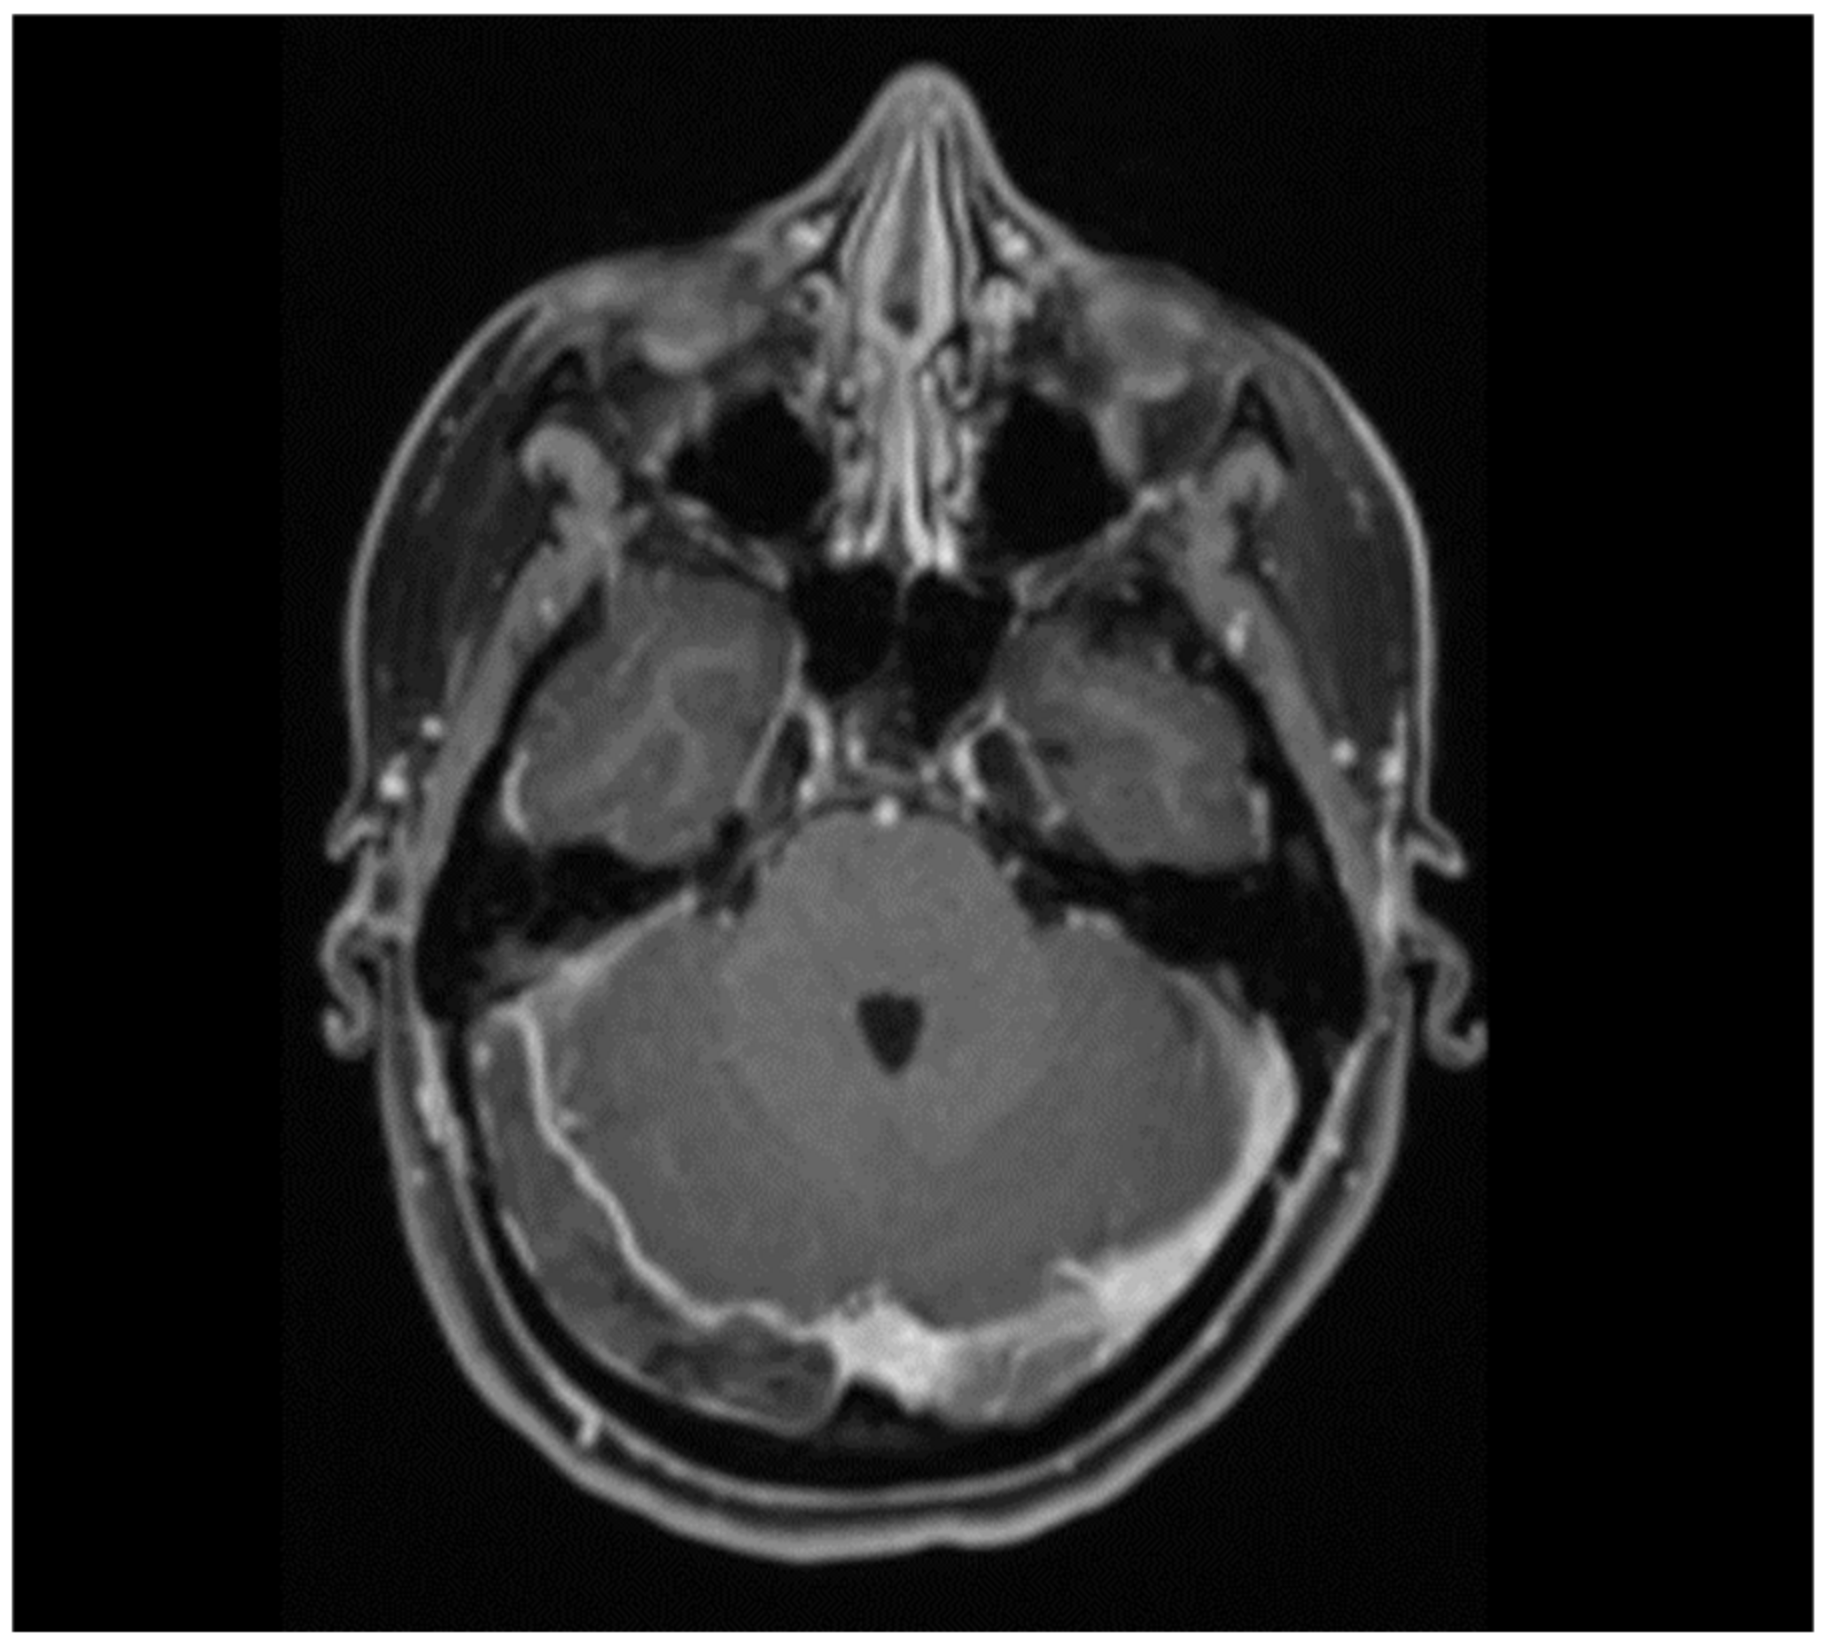

- Ikenberg, B.; Demleitner, A.F.; Thiele, T.; Wiestler, B.; Götze, K.; Mössmer, G.; Lingor, P. Cerebral venous sinus thrombosis after ChAdOx1 nCov-19 vaccination with a misleading first cerebral MRI scan. Stroke Vasc. Neurol. 2021, 6, 668–670. [Google Scholar] [CrossRef]